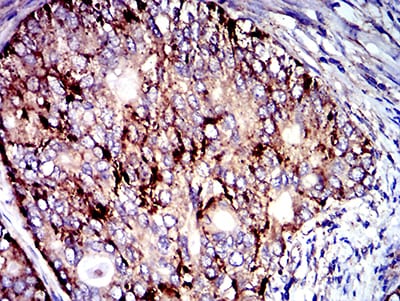

Product Image |

| IHC | 1/200 - 1/1000 |